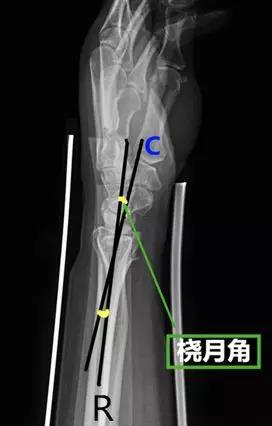

- 桡月角:在腕部侧位片上桡骨和月骨(近端与远端)中轴线的夹角。

- 正常值:0°~15°

- 临床意义:屈曲>15°提示掌曲不稳,背伸>10°提示背伸不稳。